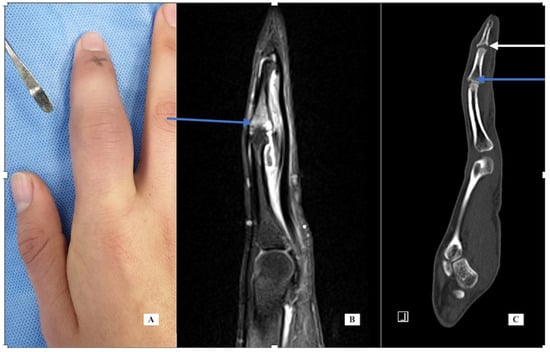

Case 2: A 30-year-old female was seen in February 2019 with left index finger pain, swelling and stiffness for one year. Her exam was notable for left index finger PIP joint swelling and reduced flexion. Her history was significant for fibromyalgia diagnosed by rheumatology. An MRI of the finger (Figure 2 left and center, T1 fat suppressed with IV contrast) shows bone marrow edema of the distal half of the proximal phalanx and mild reactive changes of the PIP joint with dorsal and volar synovitis but no tenosynovitis. The report added that “infection cannot be ruled out”. A biopsy was carried out under WALANT in June 2019. The incision was dorsal over the PIP joint using the interval between the central slip and the lateral band. An incisional biopsy of the thickened dorsal capsule was sent for pathology and cultures. Pathology showed nonspecific synovitis with mild inflammation and vascular infiltration. The cultures were all negative, including fungal and mycobacteria. After the final negative culture result, the frozen biopsy specimen was sent for PCR (16S rDNA) testing and was also negative. Additional testing by rheumatology included additional labs for inflammatory markers, Lyme serology and sexually transmitted disease (STD), all of which were negative. Infectious disease recommended additional serologic markers for Q fever, Brucella and Bartonella, all of which were negative. Because of her persistent complaints of pain and stiffness, CT was recommended. The CT scan showed marginal erosions of the index P1 distally at the origin of the radial collateral ligament (Figure 2, right). This is indicative of an underlying inflammatory condition, most likely psoriatic arthritis. She was referred to rheumatology and started on methotrexate but did not experience relief. At the time of her last evaluation, she was switched to apremilast (30 mg twice per day), a medication specifically for psoriasis treatment.

Figure 2. Case 2—MRI of the finger, sagittal view (A) demonstrating synovitis (blue arrow) and bone marrow edema of distal P1 (white arrow); coronal view (B); CT scan of the finger, coronal view (C) demonstrating marginal erosion at the radial collateral ligament origin.